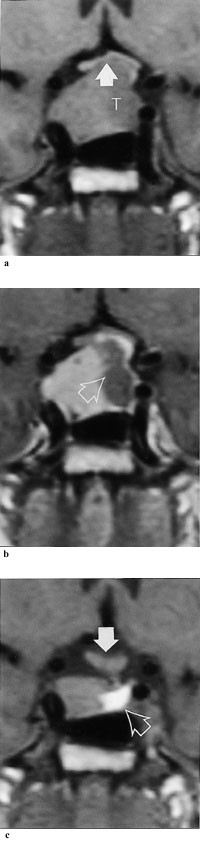

MR-undersøkelse er i dag den beste metoden for påvisning av små hypofyseadenomer (ned til 2 mm). CT-undersøkelse påviser som regel mikroadenomer ( 4 mm) og makroadenomer. Makroadenomer er spesielt viktig å påvise, da disse skal behandles av spesialist i endokrinologi med erfaring i slik behandling (tab 3).

Dopaminagonistene hemmer prolaktinsekresjonen ved å binde seg til og stimulere dopaminreseptorene på de laktotrope cellene (30). Ved langtidsbehandling av mikroprolaktinom gjenopprettes gonadefunksjon hos 80 – 90 % av pasientene (2, 31). Ved tidligere ubehandlet makroprolaktinom oppnås normoprolaktinemi hos inntil 85 % av pasientene (32), og mer enn 25 % reduksjon av tumorvolum sees hos om lag 80 % av pasientene (32, 33) (fig 1).